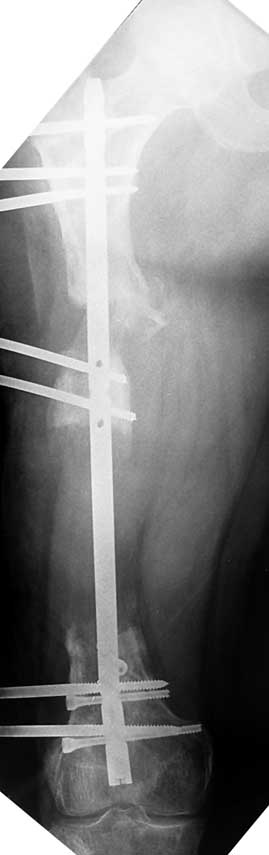

Appropriate radical debridement necessitates excision of all necrotic bone and soft tissues, and frequently causes instability at the involved extremity. The remaining bone and soft tissue defect has to be fixed and reconstructed. The distraction osteogenesis method of Ilizarov is used successfully for achievement of union, correction of the deformity, elimination of limb length inequality and reconstruction of segmental bone defects.

The duration of external fixation (external fixation index) depends on the amount of distraction required, and the extremity is prone to complications during this period. After the distraction phase is completed, the external fixator remains in place during the consolidation phase, which lasts twice as long as the distraction phase; but this period is hardly tolerated. If the external fixator is removed before sufficient consolidation is achieved, fractures, deformity and shortness will be the result. In our department, ‘lenghthening over nail’ method is used in order to decrease the external fixation index and increase patient comfort and activity level. In this method, the intramedullary nail is statically locked after the completion of the distraction phase, and external fixator is removed. The extremity is stabilized by the intramedullary nail during consolidation phase. In this way, complications due to long external fixation index or early removal of the external fixator are avoided.